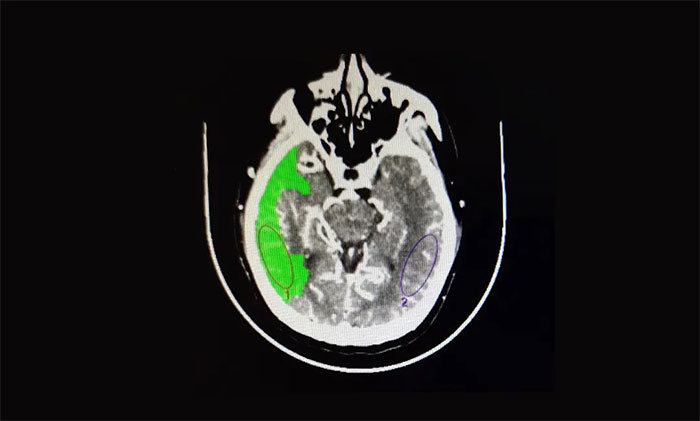

医院脑血管病病区主任张琪博士指出,患者从症状上看考虑急性大血管闭塞。急诊头颅CT平扫提示:右侧枕顶叶低密度灶;头颅CTA提示:右侧大脑中动脉M1段节段型重度狭窄;头颅CTP:右侧大脑半球脑组织灌注不足,存在缺血半暗带。

▲ CTA提示:右侧大脑中动脉M1段节段型重度狭窄

▲ 头颅CTP:右侧大脑半球脑组织灌注不足